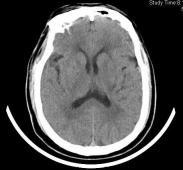

腔隙性脑梗死是一种很小的梗死灶,直径一般不超过1.5厘米。这种梗死多发生在大脑深部的基底节区以及脑干等部位。在这些部位的动脉多是一些称为深穿支的细小动脉,它们实际上是脑动脉的末梢支,又称终末支。由于深穿支动脉供血范围有限,所以单一支的阻塞只引起很小范围脑组织的缺血坏死,即形成所谓的腔隙。